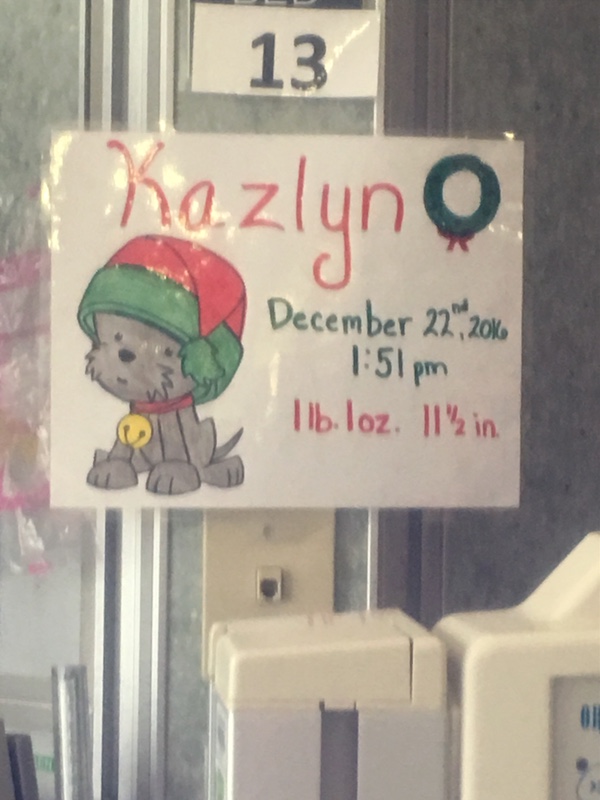

December 22nd, 2016 became the day our Christmas Miracle, Kazlyn Elizabeth, changed our life. It started when the Doctor called, requesting Alicia to get blood work and an ultrasound at one of Buffalo's finest hospitals. At 25 weeks pregnant it was routine at this point, Alicia and I both decided to make a day of it. A trip to Buffalo might as well be completed with Christmas shopping and dinner, or so we thought. It was 10AM and minutes after we arrived the nurse threw a blood pressure cuff on Alicia and it read 190s/110s, protein in her urine was record high with our nurse. Preeclampsia protocol was met, and Alicia was admitted. Everything at this point moved very quickly, I just held her hand we assured eachother that everything was going to be fine. Once Alicia became stable around 1:30pm, the nurse had to restablish a fetal heart rate, with some trouble she requested the Doctor only to discover that Kazlyn's heart rate plummeted. An emergency c-section save both Alicia and Kazlyn from placental abruption. Kazlyn came out with a cry, and was fighter before birth.

Alicia at 25 weeks and 4 days pregnant gave birth to Kazlyn Elizabeth at 0.48 Kg and 11 1/2 inches long on December 22nd, 2016 at 1:51pm.